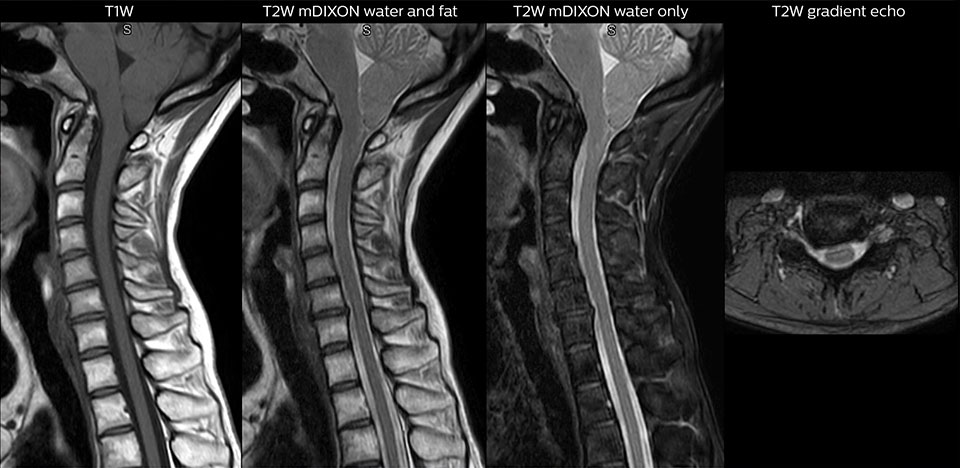

“For the thoracic and cervical spine routine non-contrast exam, for example, we perform one mDIXON T2 TSE sequence, which provides us with two outputs: the fat-and-water-together T2-weighted images, as well as the water-only sagittal T2-weighted images. And then we also perform an axial gradient echo exam.”

Cervical spine routine exam

This patient presented with headache that was worse with neck flexion and we see a Chiari 1 malformation with low-lying cerebellar tonsils as well as some degenerative cervical thrombolytic change.